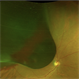

- vitreoschitic membrane

- vitreoschisis, myopic traction maculopathy

- intra operative photograph, SONY camera

- Triamcinolone enhanced visualization of vitreoschisis membrane and removal in a case of myopic traction maculopathy.